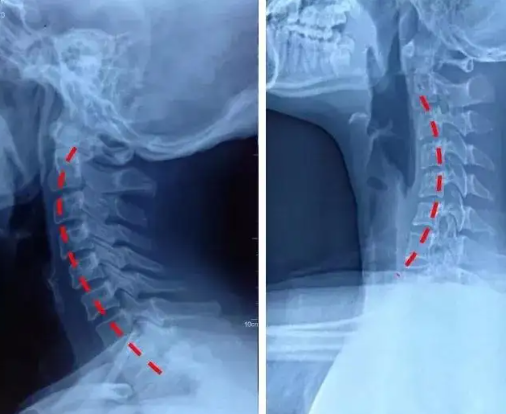

正常颈椎和反弓颈椎图

颈椎反弓的恢复对比 - 知乎